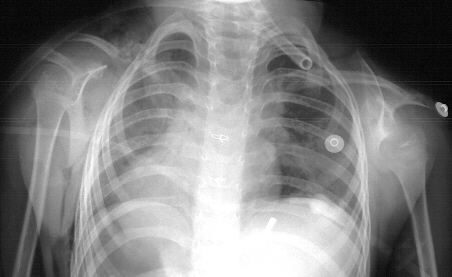

XRAYS: Demonstrate elevated left scapula worse than right,

No evidence of omovertebral bone on either side, Thoracic Kyphosis - no

other spinal abnormalities

RADIOGRAPHIC FINDINGS

- Elevated Scapula

- Associated bony deformities

- Best views - AP of both shoulders with arms abducted and adducted maximally

- Lateral cervical and thoracic spine to look for other abnormalities

- Oblique and Lateral of scapula to show omovertebral bone (1/3 of cases)